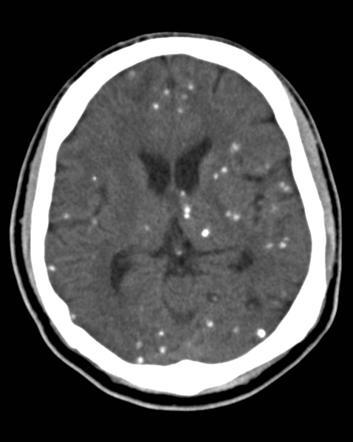

In a patient with Advanced HIV (CD4 < 100) what is a Sign of Disseminated Cryptococcus Disease?

Cutaneous Cryptococcus

In a patient with advanced HIV, (CD4 < 100) what are the Most Common Clinical Manifestations of Cutaneous Cryptococcus?

Rapid Onset of multiple Papular lesions with Central Umbilication and Central Hemorrhage/Necrosis.

What is the Most Common Clinical Manifestation in an HIV+ patient with Cryptococcal neoformans infection?

Meningoencephalitis

Cryptococcal neoformans has what structure, and is what kind of Fungus?

Encapsulated Yeast